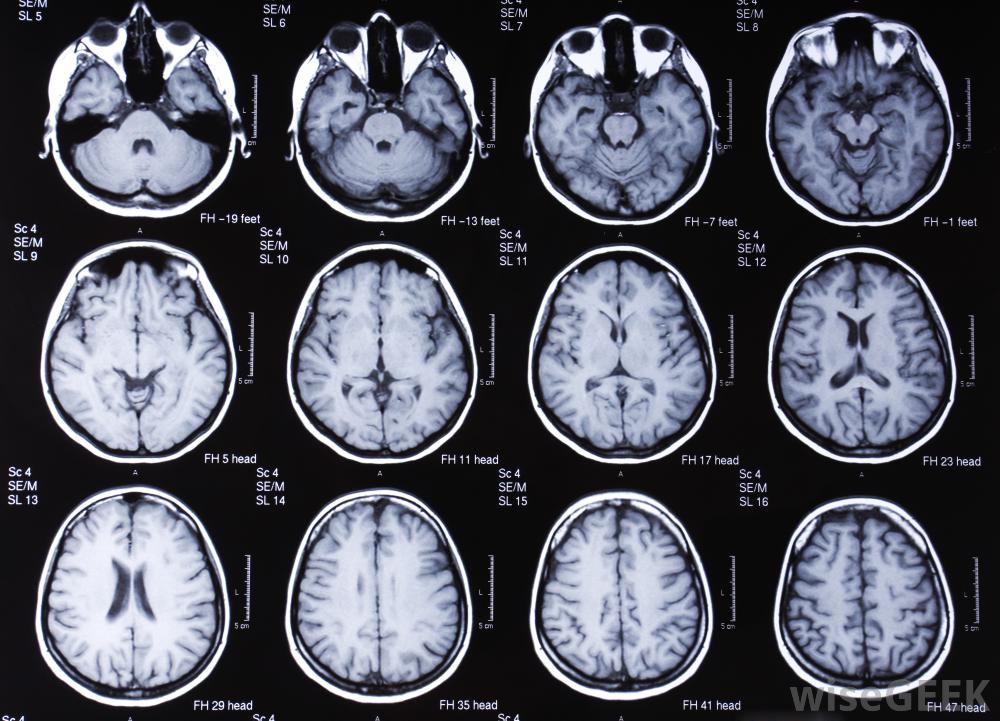

磁共振成像(MRI)是一種醫學診斷技術,它利用強磁場獲得患者身體內部的圖像。無對比度的MRI通常被稱為標準的MRI掃描,不需要向體內注射任何藥物或造影劑。增強磁共振成像包括注射造影劑以提高圖像的靈敏度。無對比度的核磁共振成像適合大多數情況,只要不需要額外的細節。無對比度的腦部核磁共振掃描核磁共振成像機利用人體內粒子的磁特性來形成圖像。核磁共振掃描是醫生可用的最詳細的診斷成像形式之一。核磁共振掃描的好處是不需要使用電離輻射,可能會對患者造成潛在傷害,盡管機器的制造和維護成本高昂。大多數核磁共振檢查都是在沒有對比的情況下進行的標準的核磁共振掃描被稱為無對比劑的核磁共振成像。這意味著磁共振成像機可以對所需區域進行成像,而無需將造影劑注入人體。在大多數情況下,除非受影響的區域很小或很難看到,否則無對比度的核磁共振成像是檢查身體內部問題所必需的帶對比度的MRI可以幫助醫生測量小腫瘤,以確定治療是否正常。無對比度的MRI可用于身體大部分部位。一些最常見的部位需要核磁共振掃描包括大腦和脊髓。關節也經常被掃描以發現損傷的軟骨和撕裂的韌帶。核磁共振機器利用體內粒子的磁性來做一個圖像。在接受檢查之前,病人通常被要求提前半小時到達。這樣放射科醫生就可以通過核磁共振來討論潛在的問題,例如,如果病人有金屬植入物,一旦使用了核磁共振儀,病人在掃描時必須避免移動。核磁共振成像需要大量的圖像,而且圖像必須清晰,這就是為什么保持靜止很重要的原因無對比度的MRI掃描提供了非常詳細的信息,盡管機器的制造和維護成本很高在某些情況下,醫生可能需要使用增強磁共振成像(MRI)來更詳細地觀察身體的某個特定區域。這需要在掃描過程中通過單次注射或靜脈滴注將對比劑"染料"注射到身體內。對比劑的目的是識別體內的任何活動性問題為了提高圖像的靈敏度,通常使用無對比度的MRIs來獲得大腦或脊髓的精確圖像如果懷疑脊髓損傷,通常需要進行MRI檢查。